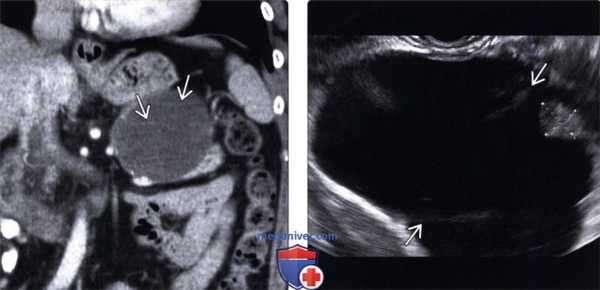

(Левый) При КТ с контрастным усилением на корональной томограмме в хвосте поджелудочной железы визуализируется четко отграниченное округлое кистозное образование с плохо различимыми внутренними перегородками.

(Правый) При эндоскопическом УЗИ в той же зоне выявлено крупное кистозное образование с внутренними перегородками и мелким интрамуральным узлом (метки измерителя), не видимыми при КТ.